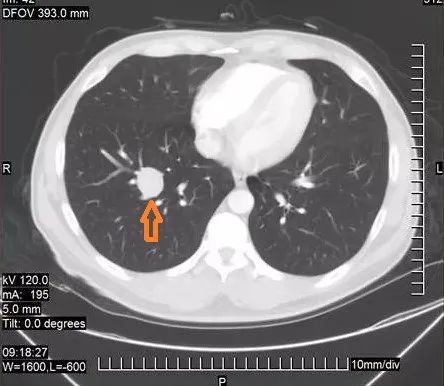

右肺上叶结节,边界清楚,边缘不整,呈浅分叶状,可见细小毛刺,邻近胸膜